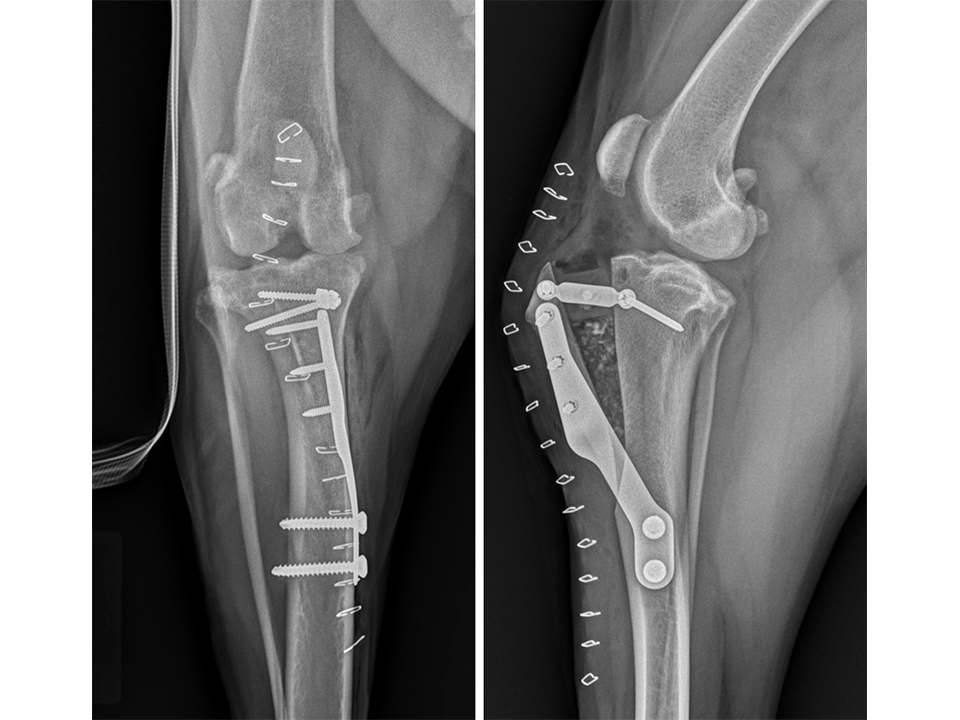

Radiographs of the right stifle (Fig 10) revealed moderate joint effusion and periarticular osteophytosis likely secondary to CrCL disease with concomitant MPL.

The right stifle joint was considered a suitable candidate for a tibial tuberosity transposition and advancement (TTTA) to stabilize the CrCL deficient stifle and realign the quadriceps mechanism with one surgical procedure. Preoperative TTTA planning was conducted as previously described and a 12 mm wedge and a size 7 plate were selected.

Following a frontal plane osteotomy of the tibial tuberosity, it was estimated that to re-align the quadriceps mechanism appropriately, 5 mm of lateralization of the tibial tuberosity would be required. The size 7 plate was contoured to fit the medial surface of the tibia, while at the same time placing an additional slight bend to the plate at the midportion so as to allow this lateralization to occur. Plate application, tibial tuberosity advancement, and trimming of the wedge were performed as described in the previous case; a 5 mm spacer was additionally attached to the cranial tab of the wedge in order to also transpose the tibial tuberosity laterally. The medial cortex of the tibia was recessed slightly using a high-speed drill immediately caudal to the distal extent of the osteotomy to allow unrestrained positioning of the additional curve in the contoured plate. Plate fixation was achieved using 2.4 mm locking and 3.5 mm standard cortical screws identical to the previous case. The wedge was secured in place using two 2.4 mm standard cortical screws with the cranial screw applied through the spacer. Stability in CrTT was ensured as was mediolateral stability of the patella. The surgical site was flushed and a bone graft inserted into the osteotomy gap (Osteoallograft Orthomix Fine). Closure was routine.

Immediate postoperative radiographs (Fig 11) revealed satisfactory implant and osteotomy positioning with the patella appropriately positioned within the femoral sulcus. There was no laxity in CrTT and the patella could not be luxated. Radiographs obtained 10 weeks postoperatively (Fig 12) revealed no evidence of implant-associated complications and smooth osseous proliferation bridging the osteotomy gap. Osteoarthritic changes within the joint were mildly progressive. Clinically at this stage, no pelvic limb lameness was evident. The range of motion of the right stifle joint was within normal limits. The stifle was stable in CrTT and the patella could not be luxated. No pain response was noted with the physical examination.